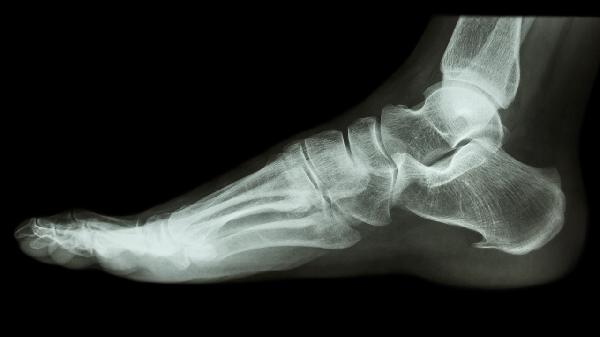

小脚趾骨头疼痛可能与外伤有关。外力撞击或挤压可能导致小脚趾骨头出现骨折、骨裂或软组织损伤,通常伴随局部肿胀、淤血和剧烈疼痛。轻微外伤可通过冷敷缓解肿胀,严重外伤需就医进行X线检查。若确诊骨折,可能需要石膏固定或手术治疗。日常生活中应避免脚趾受到外力撞击,穿硬头鞋可提供一定保护。

小脚趾骨头疼痛患者应注意足部护理,选择透气舒适的鞋子,避免长时间站立或行走。每天可用温水泡脚15-20分钟,配合轻柔按摩促进血液循环。饮食上保证钙和维生素D摄入,有助于骨骼健康。若疼痛持续不缓解或伴随明显肿胀、发热,应及时至骨科或风湿免疫科就诊,通过X线、CT或血液检查明确病因。夜间睡眠时可抬高患肢减轻肿胀,急性期尽量减少脚趾活动。